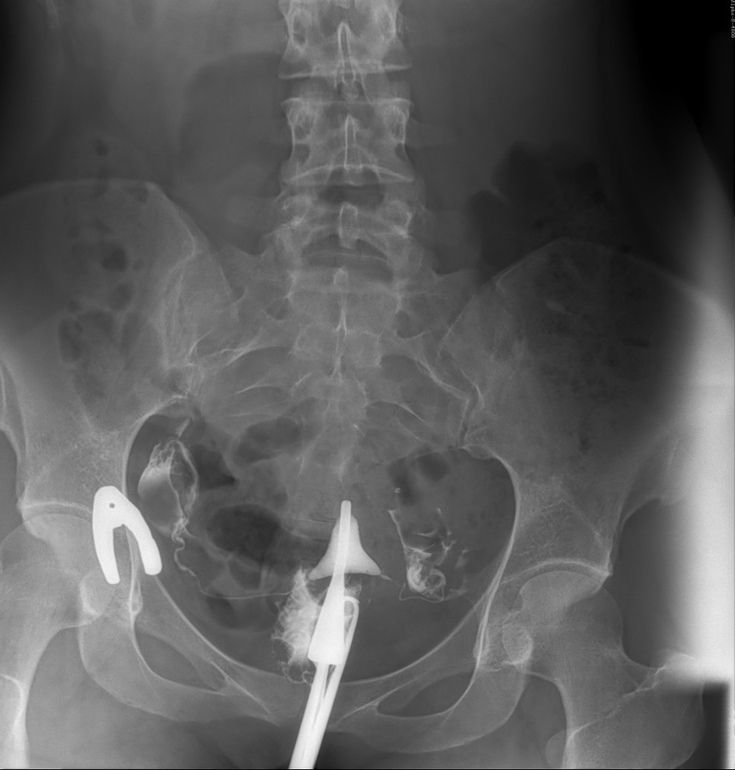

На мой взгляд обе трубы проходимы, потому что контраст вышел и справа, и слева. Видите эти белые облачка-кляксы на втором и третьем снимке? Это оно! Можете погуглить снимки других женщин и поймете, что я имею ввиду. Также есть форум рентгенологов. Можете там посмотреть на чужие снимки и свой показать. Они бесплатно прокомментируют.